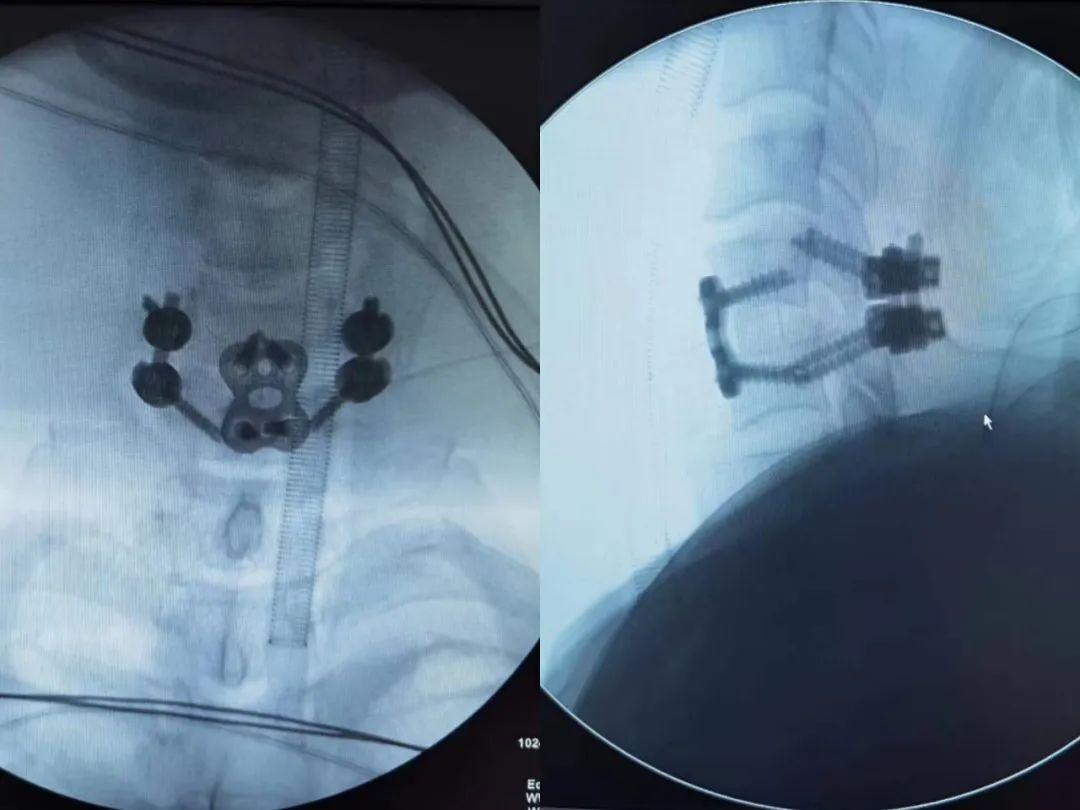

在进一步完善各项检查后,陈晓东主任带领科室团队结合患者的各项身体指征,为他设计了“前后路联合手术”。

此手术难度大、风险高,对主刀医生及医疗团队的技术要求很高。经过缜密的术前准备,陈晓东主任带领脊柱骨科团队经过8小时的奋战,最终为患者顺利实施了手术,患者术后恢复良好。